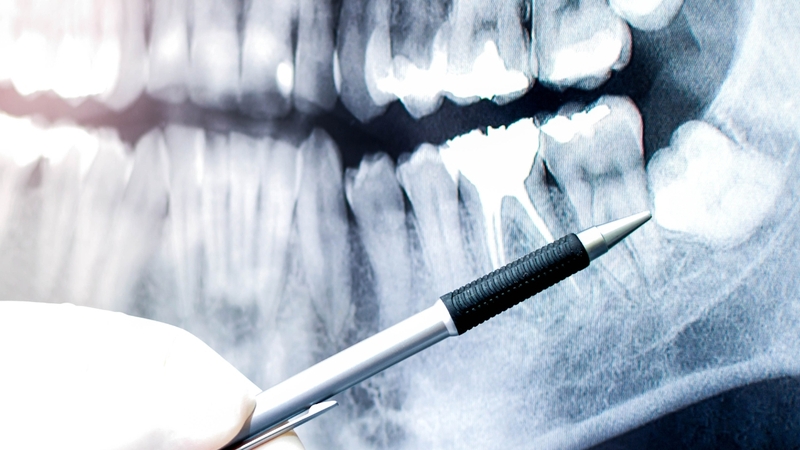

Hầu hết các trường hợp răng khôn mọc lệch đều được bác sĩ khuyến cáo nhổ bỏ để tránh biến chứng lâu dài. Tuy nhiên, quyết định nhổ hay không cần dựa trên thăm khám lâm sàng và chụp X-quang để đánh giá mức độ lệch, vị trí răng, và nguy cơ biến chứng. Trong một số trường hợp hiếm hoi, nếu răng khôn mọc lệch không gây ảnh hưởng đến sức khỏe và có thể vệ sinh tốt, bác sĩ có thể đề xuất giữ lại và theo dõi.

Quyết định nhổ hay không cần dựa trên thăm khám lâm sàng và chụp X-quang